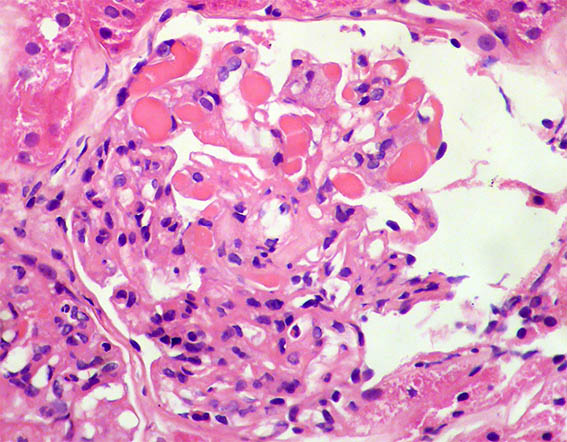

A 62-year-old woman is evaluated for erythema on both legs that has been developing for several weeks. There is no personal pathological history. On physical examination, they found systemic arterial hypertension, edema of the lower limbs, purpuric lesions on both legs, and Raynaud's phenomenon. In paraclinical tests, the hemoleukogram is normal; serum creatinine: 2.1 mg/dL, BUN: 39 mg/dL. ANA, anti-DNA, and ANCA: negative. C3: 82 mg/dL (84-180) and C4: 4.1 mg/dL (12-40). HIV and hepatotropic viruses: negative. In urinalysis there is microhematuria, leukocytes: 5/hpf, proteinuria: 4.2 g/24 hours, with mild hypoalbuminemia.

Figure 2. H&E, X400.